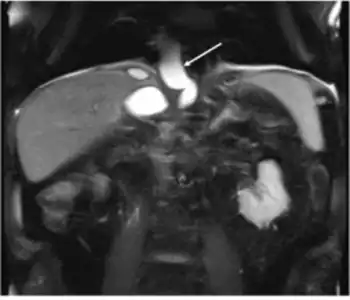

Pseudocyst extends through the hiatus opening to mediastinum

The most common and effective method of diagnosing a pancreatic pseudocyst is with a CT scan. A pseudocyst generally appears as a fluid-filled mass. In some instances, other methods must be used to distinguish between a normal cyst and a pseudocyst.[3] This is usually accomplished with endoscopic ultrasound or with fine needle aspiration.[2]

MRI and MRCP are effective methods of detecting pseudocysts, but are not regularly used because CT scans offer most of the needed information. These scans do, however, provide better contrast, which allows for better characterization of fluid collections, depicting debris within the collections, and detection of bleeding.[2]